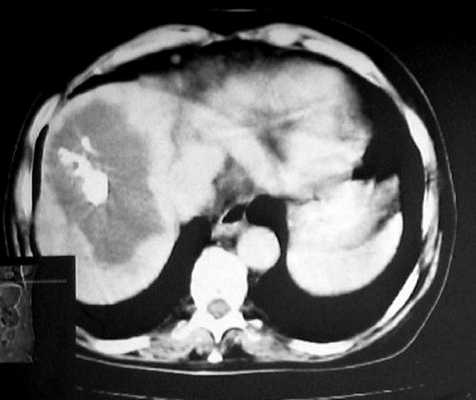

В нашем случае при ультразвуковом исследовании брюшной полости выявлено атипичное строение гемангиомы, динамическая компьютерная томография указывает на типичную гемангиому (рис. 2а, б). При этом важно знать, что только приблизительно в 54% случаев у больных с гемангиомами имеет место характерная перфузия с центростремительным усилением и поздним заполнением [20]. Однако в связи с тем, что этот тип усиления встречается только у 1,6% первичных и вторичных злокачественных опухолей печени, определение структуры данного усиления позволяет уверенно дифференцировать гемангиомы от злокачественных печеночных опухолей [20].

Рис. 2. КТ печени.

а) До контрастирования - в левой доле печени видно большое образование округлой формы.

КТ брюшной полости. Печень увеличена в размерах, неоднородная по эхоструктуре, признаков портальной и билиарной гипертензии нет. В правой доле печени, занимая практически всю долю, определяется дополнительное объемное образование, неоднородно пониженной плотности, с неровными четкими контурами, размером 143х93 мм. После введения контрастного вещества образование неравномерно накапливает его от периферии к центру, в виде языков пламени. В центре образования определяется участок равномерно низкой плотности, продолговато-ветвистой формы, с четкими контурами (гиалиновая щель). В центре образования видны участки кальцификации. В отсроченной фазе образование продолжает неравномерно накапливать контрастное вещество, максимальное его накопление отмечено в центре. Поджелудочная железа без особенностей. Селезенка нормального размера, структурно не изменена.

Заключение: гигантская кавернозная гемангиома правой доли печени (рис. 2).

а) Паренхиматозная фаза.

б) Паренхиматозная фаза.